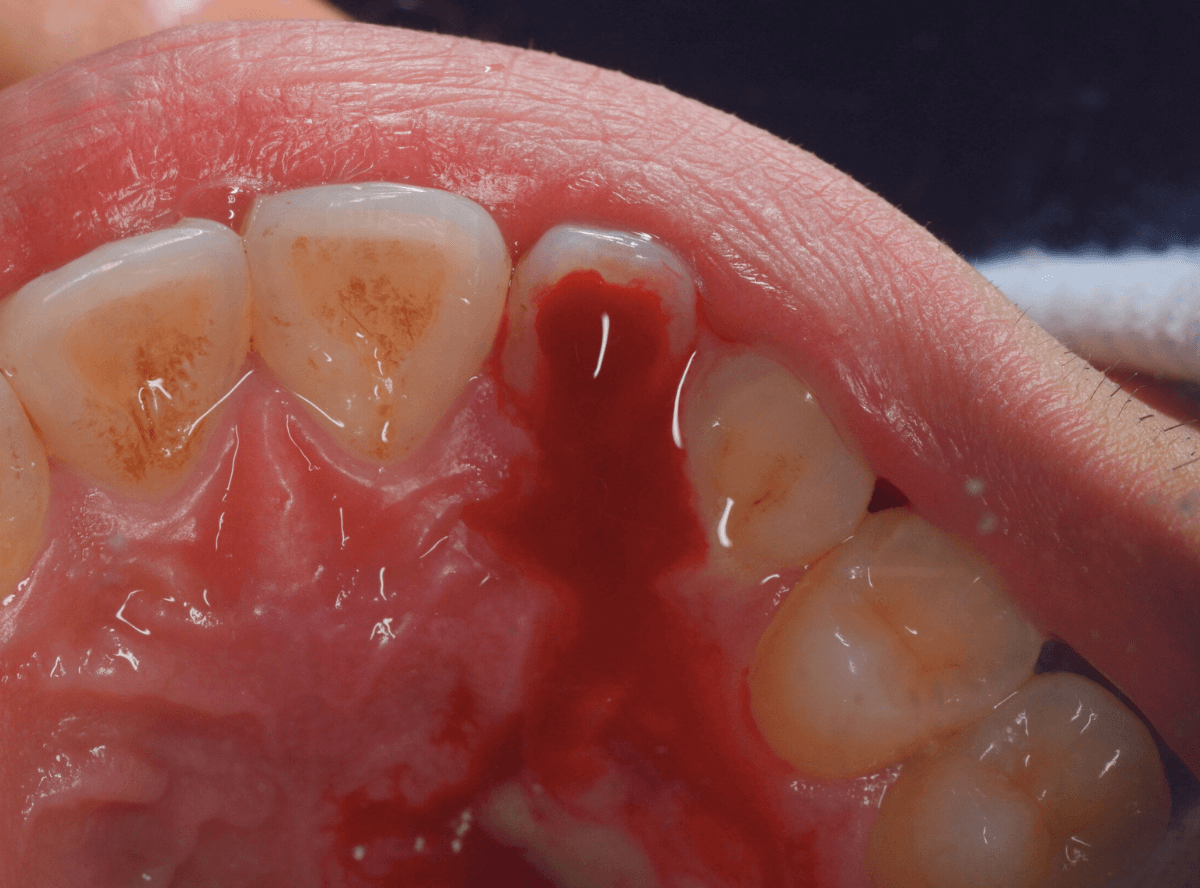

痛みをとるために、歯の後ろに小さな穴を開けてガスの抜け道を作ってあげます。

すると、中から大量の膿、その後血が噴き出してきました。

見た目は少々壮絶ですが、この状況になれば、まずは一安心です。